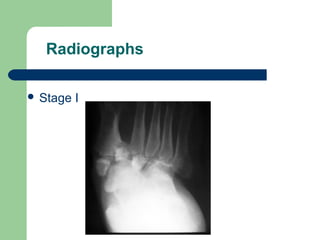

Radiographs

 Stage I